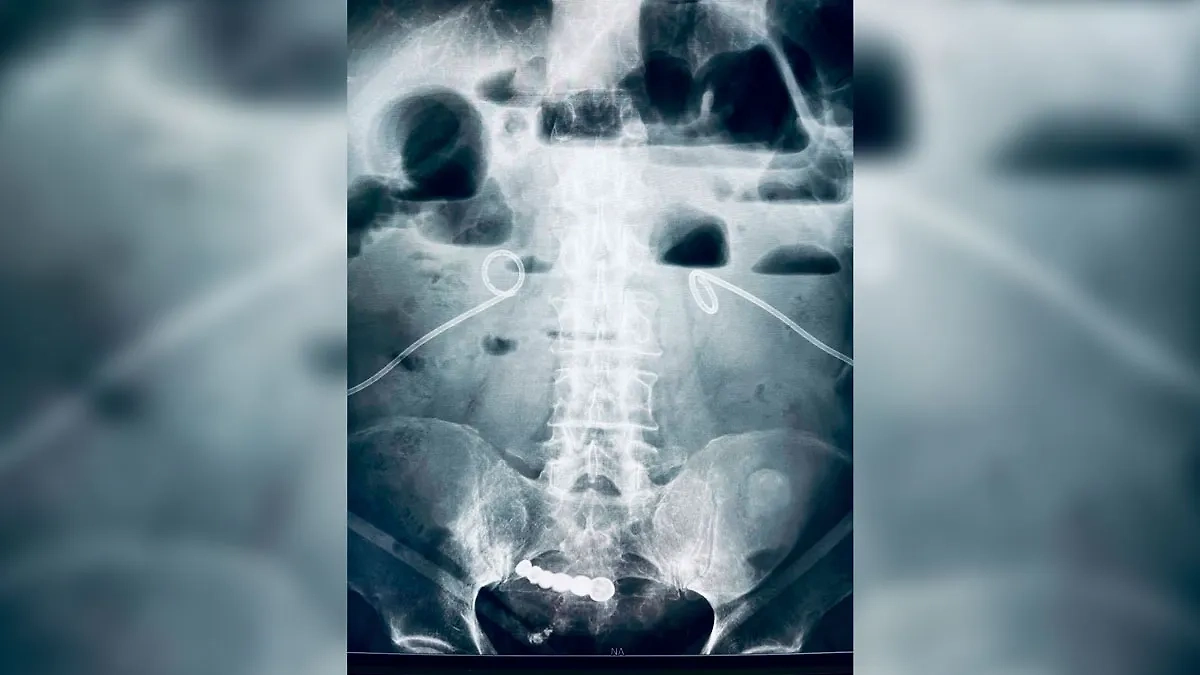

Рентген, на котором видно вставную челюсть в животе пациента. Фото © t.me / Беглов_Zdrav

"Кемеровчанин обратился в больницу с острой болью в животе. На рентгене врачи обнаружили "зубы". Выяснилось, что несколько лет назад дедушка проглотил вставную челюсть. Боли не было — и он не пошёл к врачам. Инородный предмет долгое время не доставлял никаких неудобств. Хирурги больницы удалили протез малоинвазивным методом. Пациент уже дома", — говорится в публикации Беглова.